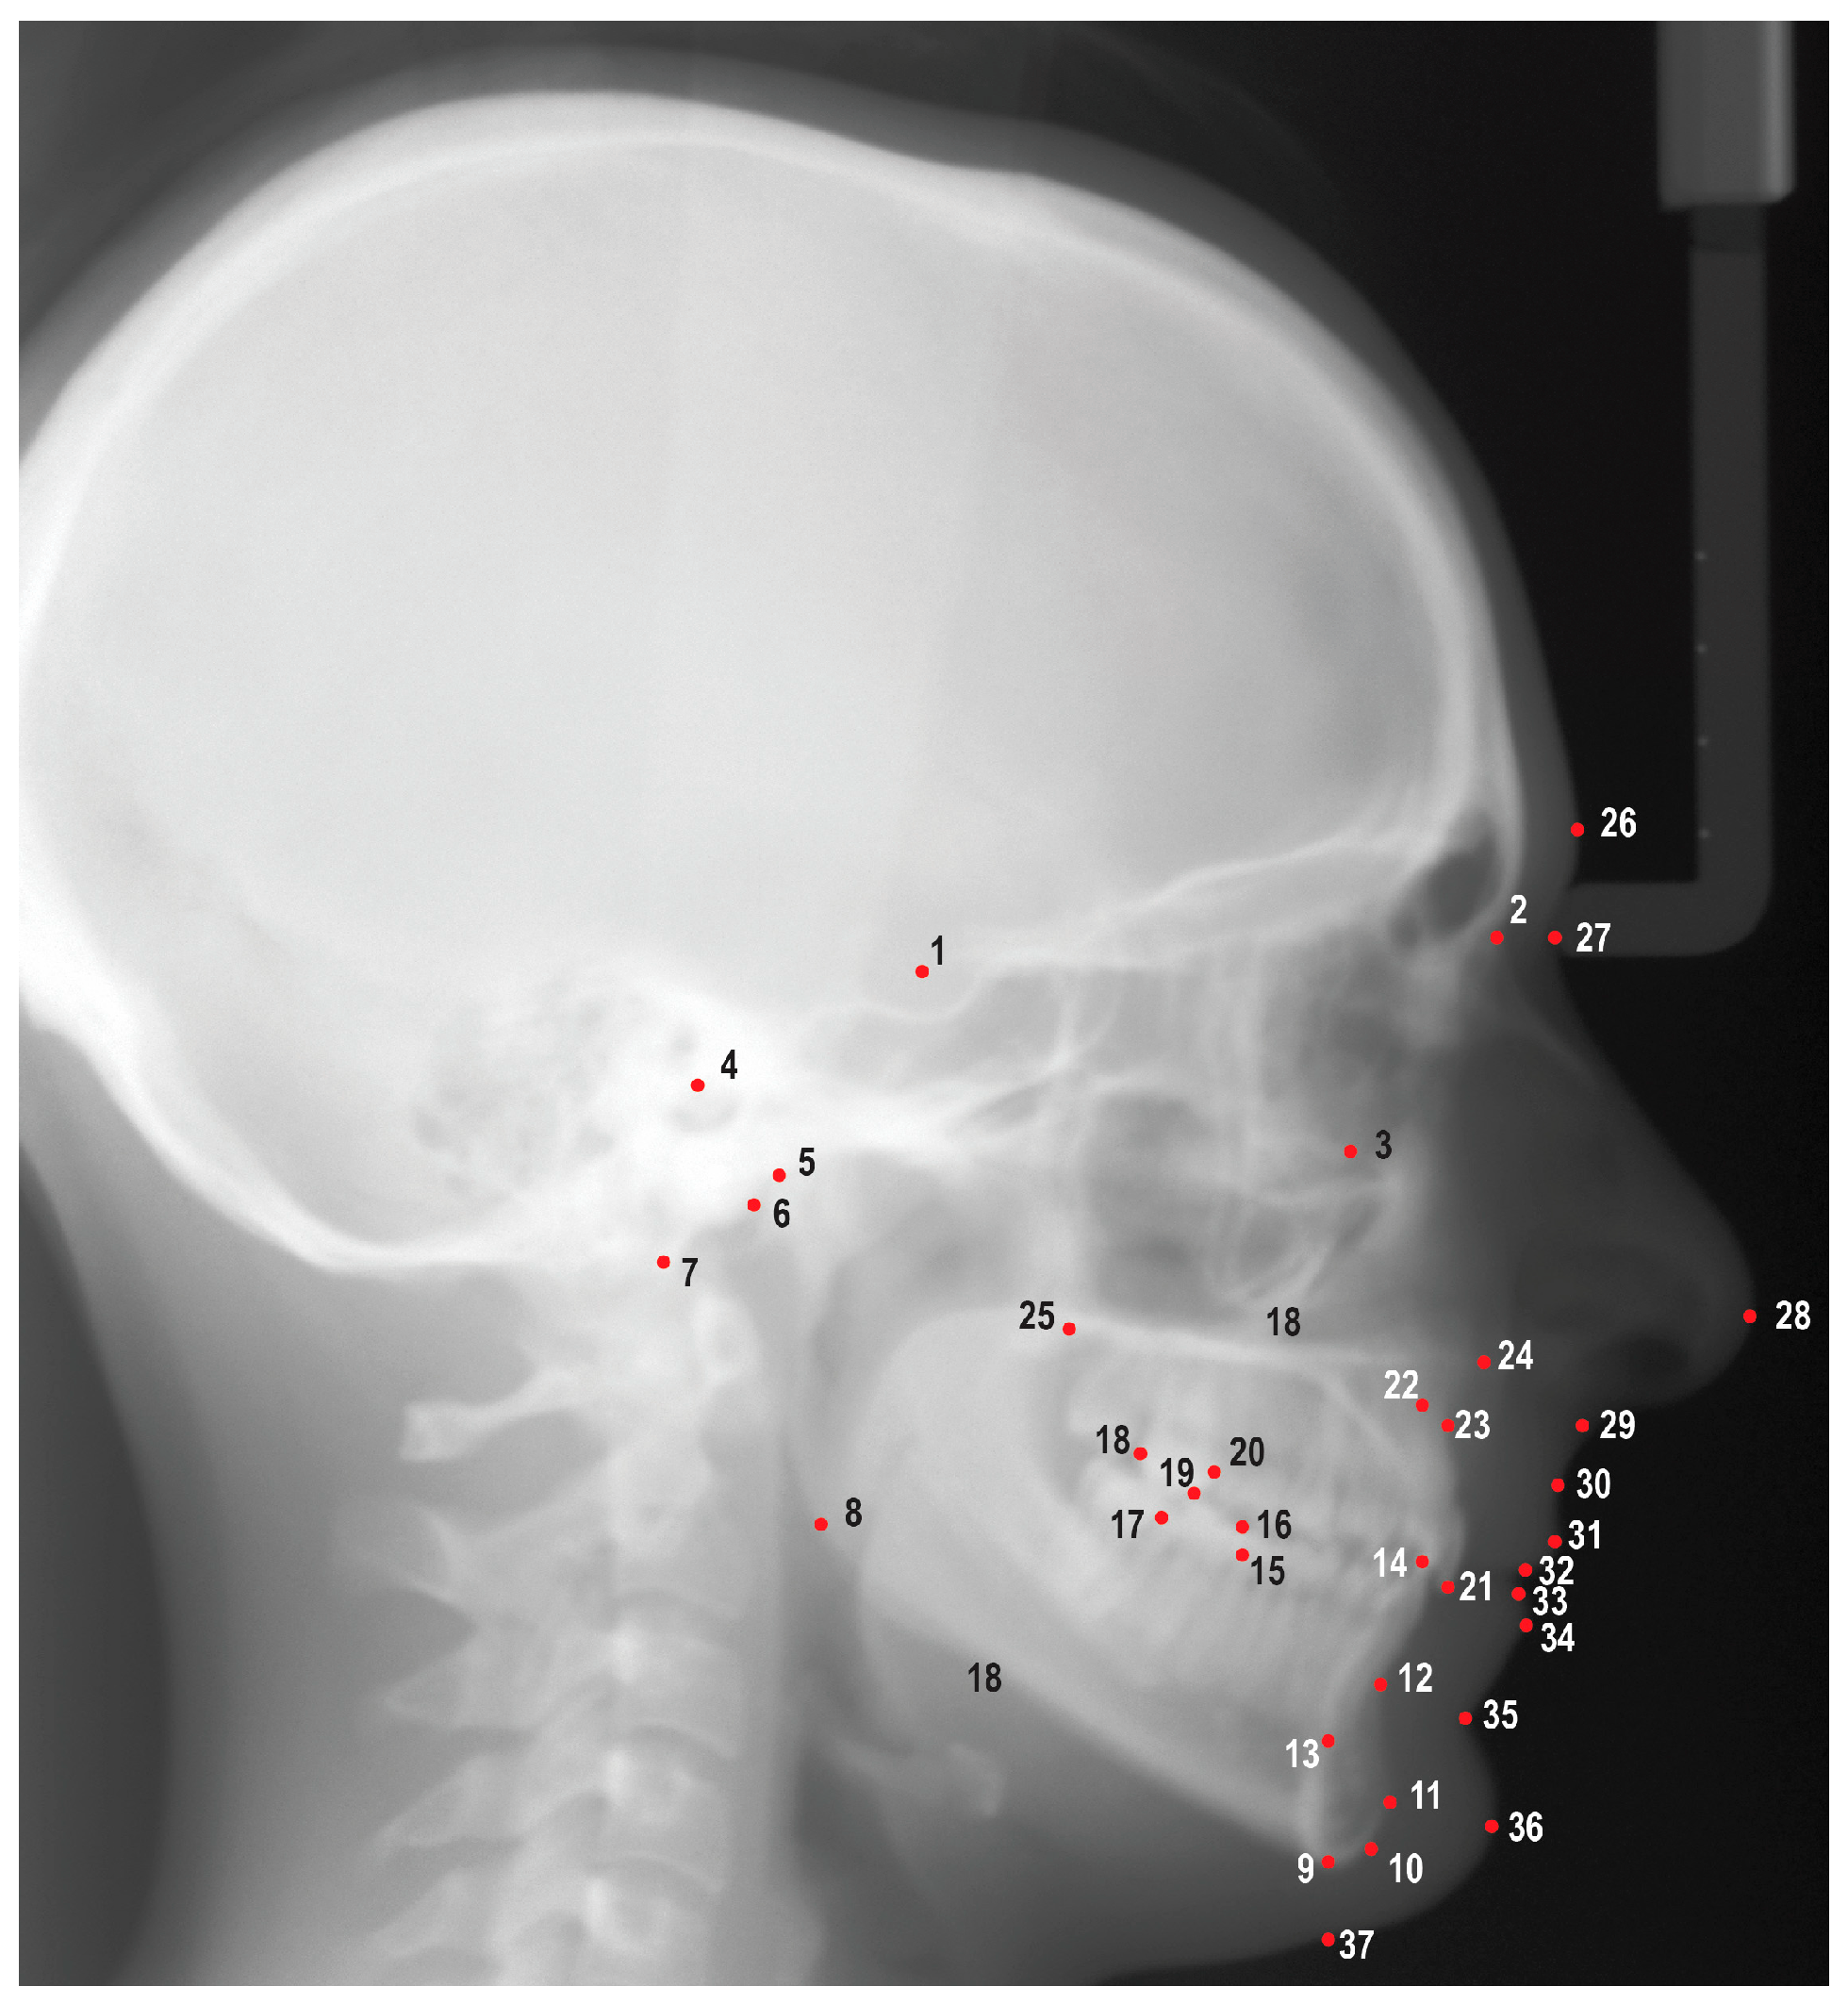

Digital images from the AAOF repository were uploaded into Dolphin Imaging v. 11.95 (Dolphin Imaging and Management Solutions, Chatsworth, CA, USA) and were traced by a single investigator (M.P.) using 25 hard tissue landmarks and 12 soft tissue landmarks (Figure 1). A total of 47 linear and angular measurements were measured and recorded; definitions of the measurements are listed in Table S1. Images were scaled by using fiducial data embedded on the images as described in reference material provided by the AAOF. Fiduciaries are reference marks located on the images with known coordinate values allowing the user to compute the scale of the image. The demographic and cephalometric data were subsequently entered into a spreadsheet and securely stored in a cloud service (OneDrive, Microsoft Co., Redmond, WA, USA). To evaluate the repeatability of measurements, a research randomizer was employed to randomly choose 10 images for retracing. The ICCs were utilized to assess the repeatability of these measurements.

Figure 1. Cephalometric landmarks used in this study. 1. Sella (S), 2. Nasion (N), 3. Orbitale (Or), 4. Porion (Po), 5. Condylion (Co), 6. Articulare (Ar), 7. Basion (Ba), 8. Gonion (Go), 9. Menton (Me), 10. Gnathion (Gn), 11. Pogonion (Pog), 12. B point (B), 13. Lower incisor root apex (L1a), 14. Lower incisor incisal edge (L1i), 15. Mesial of lower first molar (L6m), 16. Mesiobuccal cusp of lower first molar (L6mb), 17. Distal of lower first molar (L6d), 18. Distal of upper first molar (U6d), 19. Mesiobuccal cusp of upper first molar (U6mb), 20. Mesial of upper first molar (U6m), 21. Upper incisor incisal edge (U1i), 22. Upper incisor root apex (U1a), 23. A point (A), 24. Anterior nasal spine (ANS), 25. Posterior nasal spine (PNS), 26. Glabella (G), 27. Soft tissue nasion (N′), 28. Pronasale (Pn), 29. Subnasale (Sn), 30. Soft tissue A point (A’), 31. Upper lip (Ls), 32. Stomion superioris (Ss), 33. Stomion inferioris (Si), 34. Lower lip (Li), 35. Soft tissue B point (B’), 36. Soft tissue pogonion (Pog′), 37. Soft tissue menton (Me′).